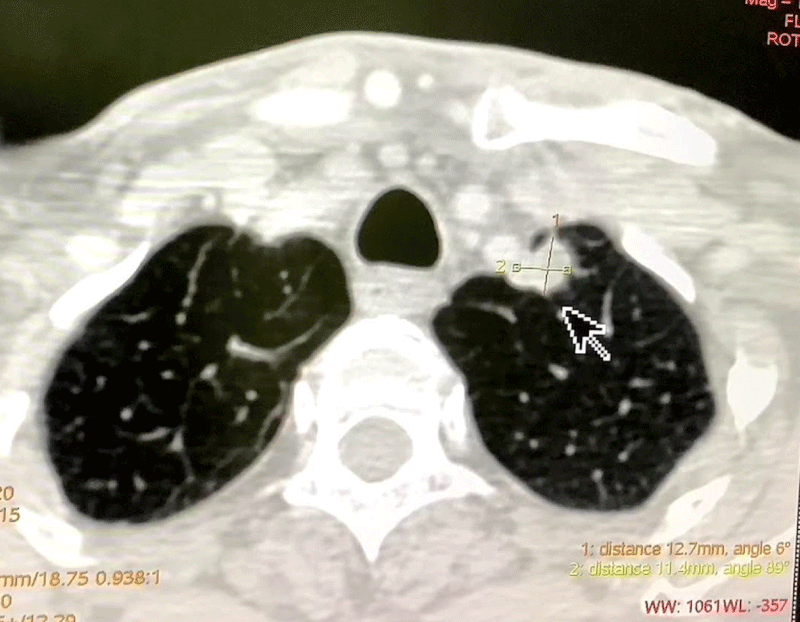

Our data of 150 pre-operative Oral Cavity Squamous Cell Carcinoma patients from 15th April to 31st July was analyzed. The patients were admitted 2 days before the date of surgery for initial assessment by RT-PCR testing. The patients with a negative RT PCR report were then subjected to HRCT Thorax and only if there were no signs suggestive of a COVID-19 infection on the HRCT scan as well, the patients were taken up for surgery. Based on the CT findings, the level of suspicion of COVID-19 infection was graded using CO-RADS classification (Table 1) (Figures 2,3). The detection rate of COVID-19 infection based on the initial RT-PCR and HRCT Thorax was compared (Figure 1). The purpose of study was explained and informed consent has been taken from patient. The ethical clearance was obtained from ethical subcommittee of institute before commencement of study.

Figure 2: HRCT Thorax (CO-RADS 1) No abnormality detected.